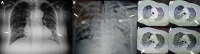

Human coronavirus HKU1 (HCoV-HKU1) is a RNA virus which gets in the human cells by binding to the receptor of N-acetyl-9-O-acetylneuraminic acid. Human Coronaviruses (HCoVs), including HCoV-HKU1, are globally found. HCoV-HKU1 is responsible for upper and lower respiratory tract infections, usually with mild symptoms. In severe cases, HCoV-HKU1 can cause life-threatening respiratory illness especially in vulnerable hosts such as elderly, children and immunocompromised patients. In Greece, Respiratory Syncytial Virus (RSV) and influenza are the most common viruses causing respiratory tract infections. Traditionally, HCoVs are responsible for less than 3% of respiratory infections in Greek population. HCoVs 229E and OC43 have been shown to circulate in Greece. We report the first case of lung infection in an immunocompromised woman due to HCoV-HKU1, that has never been before detected in Greece. HCoV-HKU1 is related to severe disease even in healthy individuals and must be considered in the differential diagnosis of severe respiratory infections.